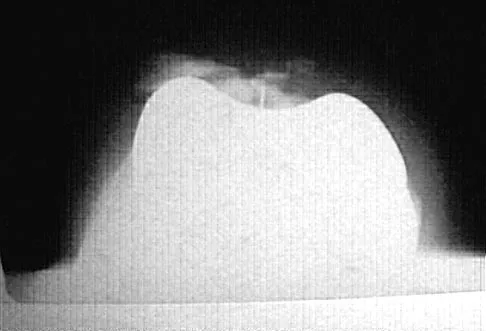

Figure 38 shows the radiograph of a 75-year-old woman who has had right shoulder pain, difficulty sleeping on the affected arm, and difficulties performing activities of daily living for the past 6 weeks. Initial nonsurgical management includes analgesics, a subacromial cortisone injection, and gentle range-of-motion exercises. However, these modalities have failed to provide relief, and the patient reports that she is unable to elevate her arm. Her pain is worse and she would like the most reliable treatment method for pain relief and functional improvement. What is the best surgical treatment?

Explanation